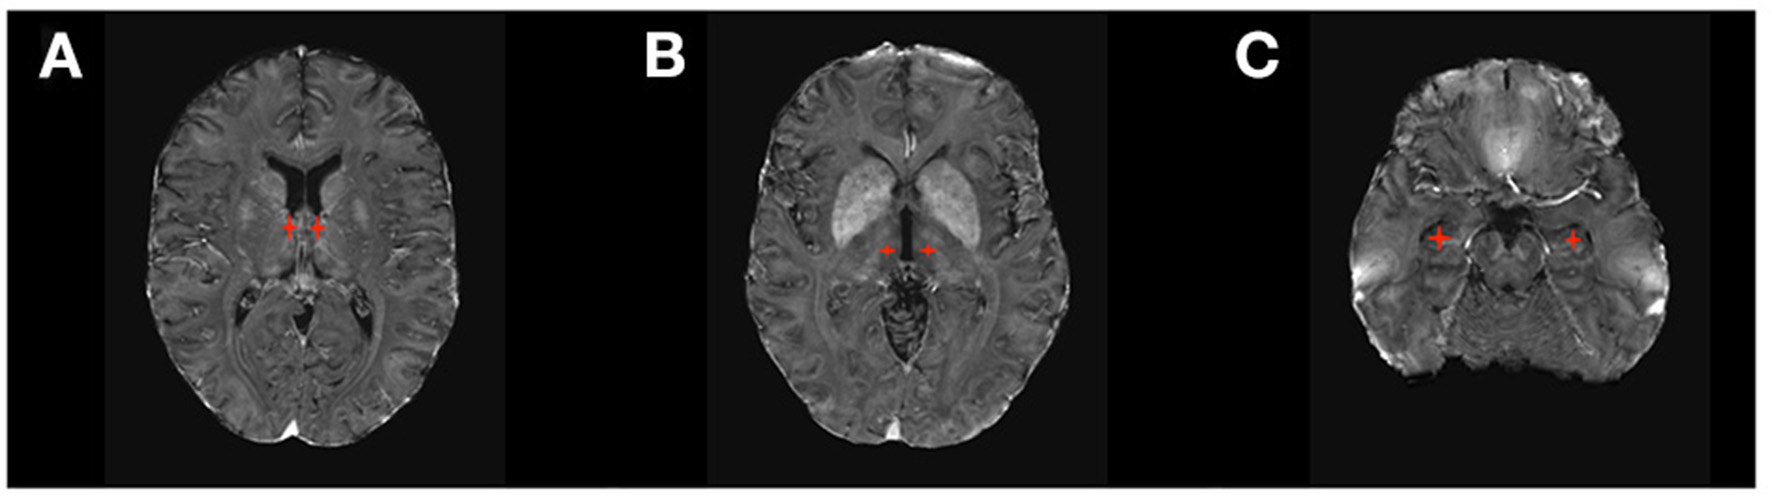

Figure 3

DBS targets in Psychiatry. (A) Ventral Capsule/Ventral Striatum (VC/VS) and Anterior Limb of the Internal Capsule (ALIC); (B) subcallosal cingulate gyrus including Brodmann area 25 (SGC25); (C) Subthalamic Nucleus (STN).

Prospective studies, retrospective reviews, and meta-analyses have demonstrated the efficacy of DBS in severe or extreme obsessive compulsive disorder (OCD) (38–40). Several targets, including ventral capsule/ventral striatum (VC/VS), anterior limb of the internal capsule (ALIC), and STN have been investigated for OCD (41, 42) (Figure 3). Outcomes are generally comparable across all implantation sites (Table 1), with an average improvement in OCD symptoms of 45% on the Yale Brown Obsessive Compulsive Inventory (53). Previously investigated predictors of outcomes, including presence or absence of hoarding disorder, intra-operative mirth or reflexive smile, and age at onset of symptoms, are inconsistent predictors of response and appear inadequate to inform clinical decision-making (38). Recent studies have investigated individualized DBS targeting for OCD using diffusion tensor imaging (DTI) and probabilistic tractography (54, 55). White matter pathways in the anterior limb of the internal capsule can be variable, and modeling the fibers may allow for localization of fibers of interest for OCD treatment, such as those connecting the nucleus accumbens and ventral striatum to target areas in the orbitofrontal cortex and medial prefrontal cortex (56).